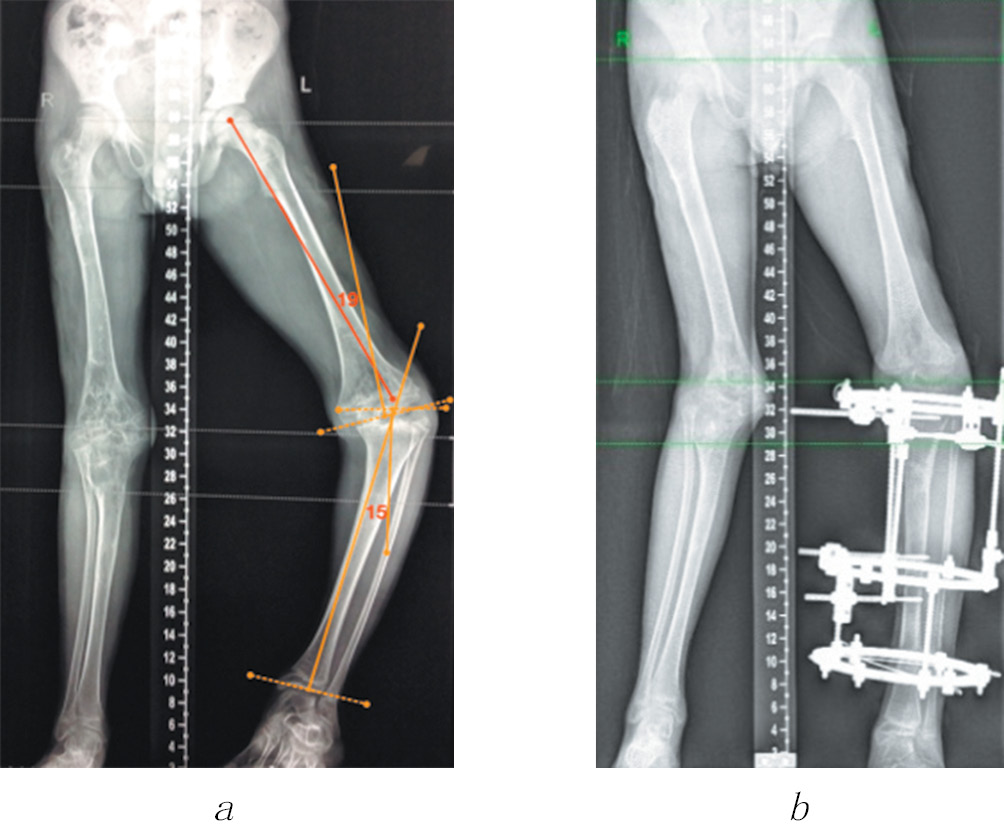

In four cases among those presented, the controlled growth technique was used to prevent the recurrence of deformity and correct the length of the fibula in dysfunction of the tibial growth zones (Fig. 6). After analyzing the literature data and own cases (recurrence of valgus deformity of the knee joint 2 and 4 years after corrective osteotomy of the femur and tibia), we concluded that temporary epiphysiodesis of the remaining functioning sections of growth zones is advisable. However, given the small number of cases, it is premature to evaluate the long-term results of temporary epiphysiodesis.

Fig. 6. Consistent application of controlled growth techniques (a) and compression-distraction osteosynthesis (b) to correct deformities of segments of the right lower limb